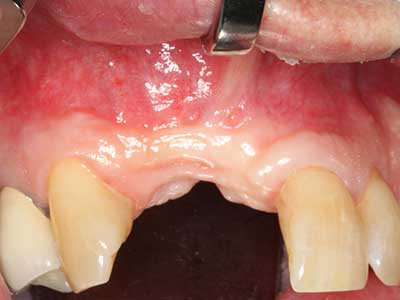

Piezo surgery has additional advantages when harvesting bone blocks. In addition to the high precision with osteotomy described above, the use of the thin saw tips specifically minimizes loss of material. Greater loss of material during harvesting can be expected with the thicker instrument tips, particularly when using Lindemann drills (Lakshmiganthan, Gokulanathan et al. 2012). The basal separation, which is necessary particularly for retromolar block transplants, is simplified by specially designed rectangular saws, with the result that piezo surgery is viewed as a precise, simple and safe procedure for harvesting retromolar bone blocks (Happe 2007) (Fig. 1-12).

Indication: Bone splitting